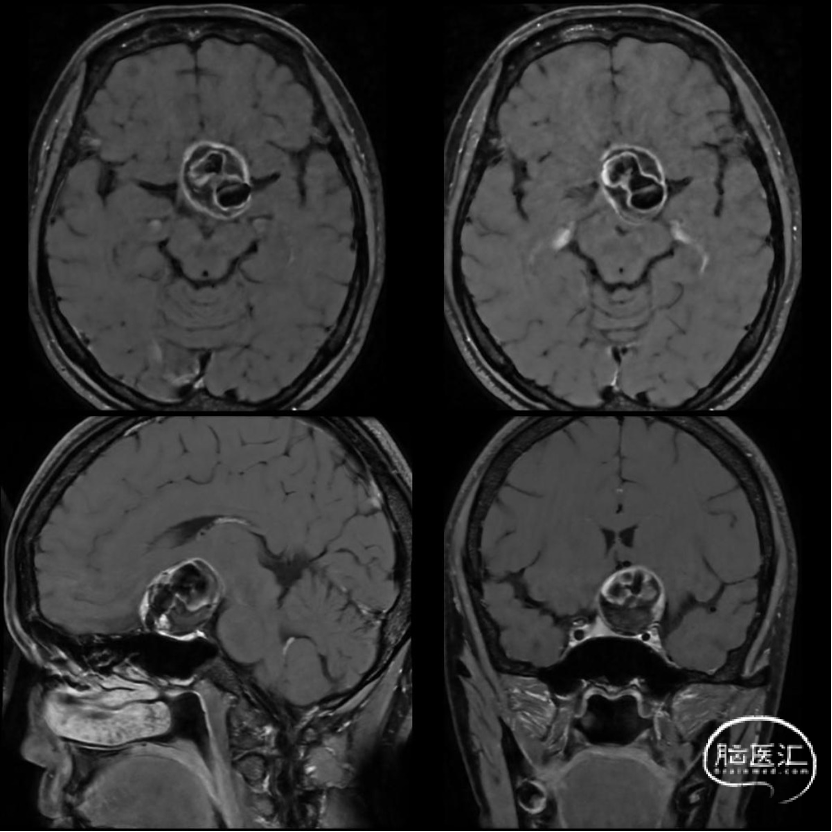

增强高分辨MRI

动脉瘤体积较大,且有增大趋势,需行孤立术保证动脉瘤内无血流。

2.本例患者动脉瘤体巨大,颈内动脉受累瘤化明显,密网支架放置中极易内陷入瘤腔,远端锚定不稳,最终导致支架释放失败;而支架远端落入瘤腔后,血流导向效果使瘤体进一步增大,视力受损症状加重。

3.搭桥血流替代后孤立是治疗此类介入复发、血栓化巨大的动脉瘤的终极方式。只有孤立动脉瘤,使瘤体彻底的“去血化”后,结合切开减压,才能预防瘤体增大形成的占位效应。本例术前造影显示先后交通动脉开放代偿较差,故术者选择需高流量搭桥替代颈内动脉血流,保证充足脑血流灌注。下颌下隧道走行桡动脉,可缩短桡动脉所需长度,预防术后压迫。